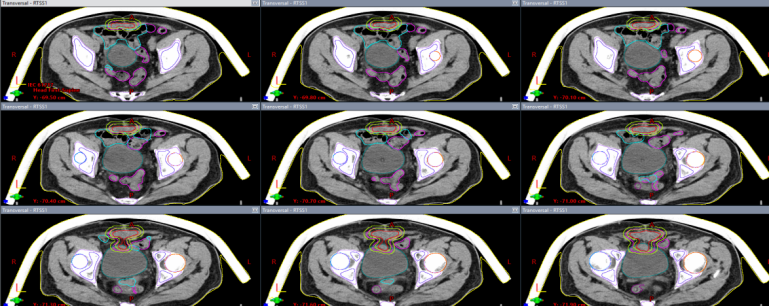

入院体查:腹壁可触及质韧包块约60×38mm,脐窝渗液,原手术切口瘢痕破溃结痂。脐周持续性疼痛显著,严重影响睡眠及生活质量。结合患者高龄、既往放疗史,属再程放疗高风险病例,常规放疗难以在靶区覆盖与正常组织保护间取得平衡,治疗难度极高。完善检查后,经我院重离子中心多学科专家联合研判病情,依据脐尿管恶性肿瘤诊疗指南及患者临床特征,制定个体化重离子放疗方案:靶区精准覆盖脐尿管全程及膀胱复发病灶,采用分段照射模式,第一程大范围照射,第二程缩野补量。该方案既满足局部根治性剂量要求,实现对肿瘤细胞高效杀伤,又最大限度降低膀胱、腹壁等正常组织受照剂量,显著降低再程放疗并发症风险,兼顾疗效与安全性。